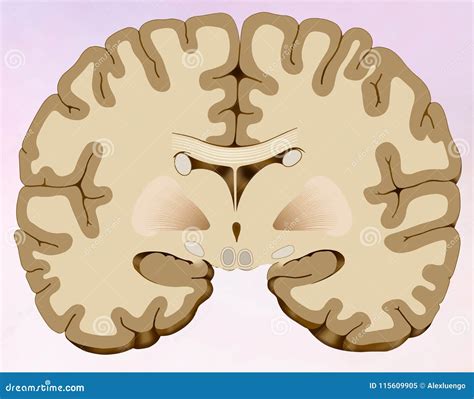

Understanding the intricacies of the human brain is a fascinating journey that has captivated scientists, researchers, and enthusiasts alike. One of the most revealing methods to study the brain is through a coronal cut of brain. This technique involves slicing the brain horizontally, perpendicular to the long axis, providing a detailed view of its internal structures. This blog post delves into the significance of coronal cuts, the structures visible in these sections, and their implications for neuroscience and medical diagnostics.

A coronal cut of brain is a cross-sectional view obtained by slicing the brain perpendicular to the long axis, from front to back. This method allows for a comprehensive examination of the brain’s anatomy, revealing various structures and their relationships. The coronal plane is particularly useful for studying the brain’s symmetry and the distribution of different regions.

A coronal cut of brain reveals a wealth of information about the brain’s anatomy. Some of the key structures visible in these sections include:

• Cerebral Cortex: The outer layer of the brain, responsible for higher cognitive functions such as thinking, memory, and language.

• White Matter: The inner layer of the brain, composed of myelinated axons that connect different regions of the brain.

• Basal Ganglia: A group of structures involved in motor control, learning, and reward mechanisms.

• Thalamus: A relay center for sensory information, connecting the brainstem to the cerebral cortex.

• Hippocampus: A structure crucial for memory formation and spatial navigation.